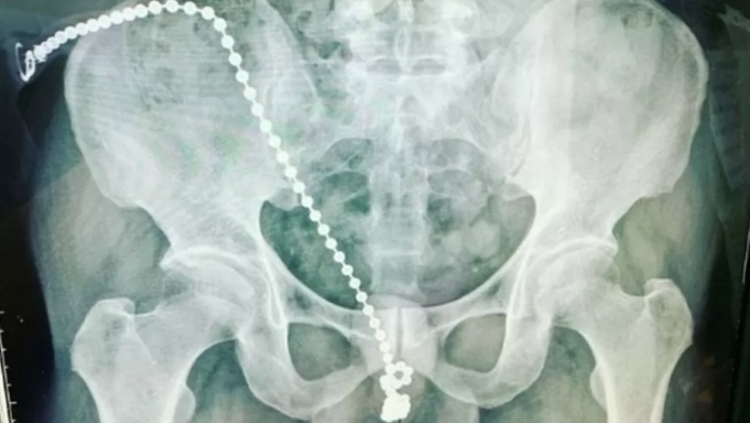

Um homem de 30 anos foi parar no hospital com dores agudas após ter introduzido uma corrente de bolinhas de metal na uretra. O caso ocorreu em Taiwan.

Ele precisou ser submetido por uma cirurgia e disse que introduziu o objeto para aumentar o prazer na hora da masturbação.

A corrente estava embutida dentro do órgão sexual e ele não conseguiu remover por receio de machucar mais.

O urologista que tratou do paciente contou que a equipe médica precisou abrir o pênis dele e desatar o nó que se formou na corrente antes de reconstruir a uretra do paciente. Todo procedimento foi bem-sucedido.